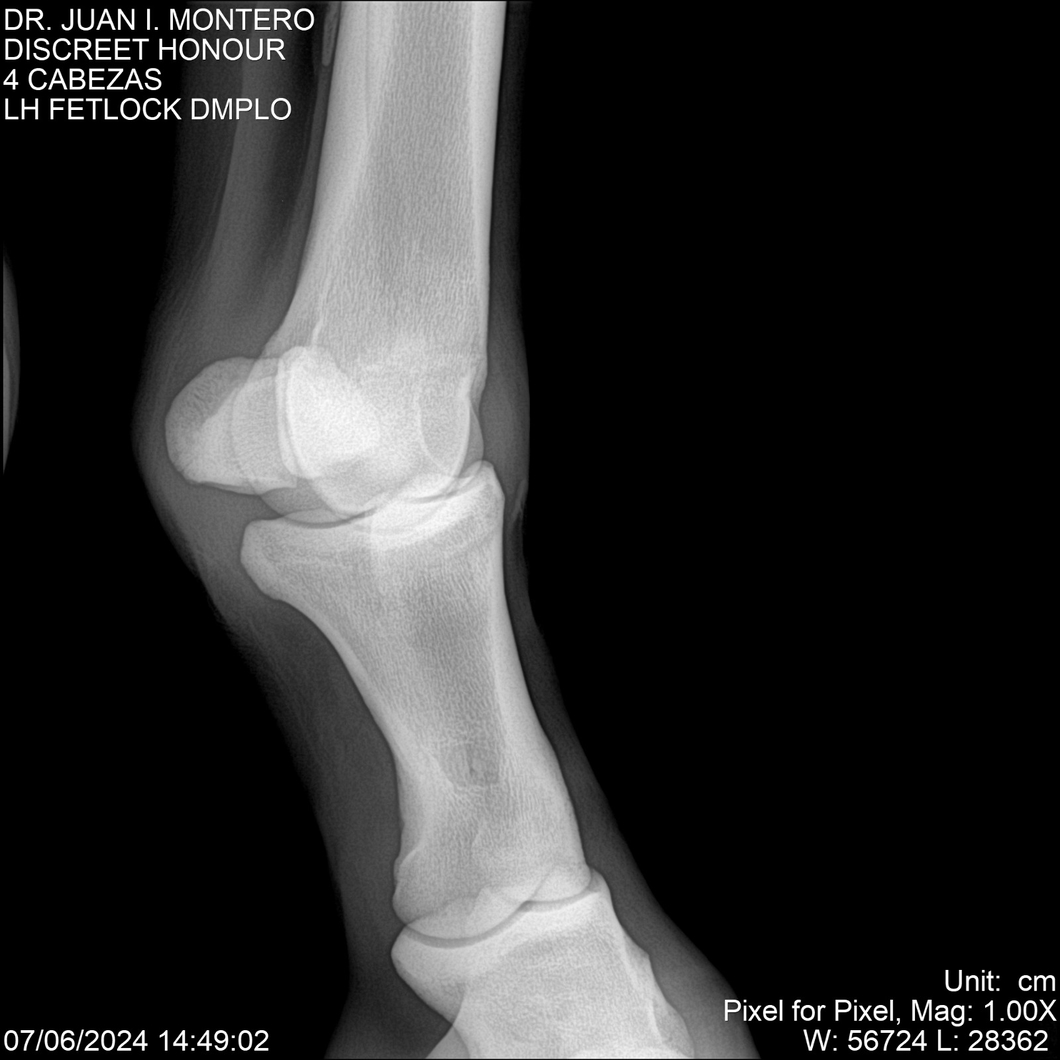

LOTE 6, DISCREET HONOUR 🔥 🔥 🔥 Lote Anterior Volver al remate Lote Siguiente Ficha Contacto Montevideo - Ficha del Lote Identificador: #281093 Categoría: Yeguarizos Montevideo - 82 Visualizaciones ClicData Contacto Empresa: Abelenda N. R., Walter Hugo Nombre*: Teléfono* : E-mail* : Mensaje Enviar Registrese gratis Este contenido Exclusivo está disponible sólo para usuarios registrados Ingresar